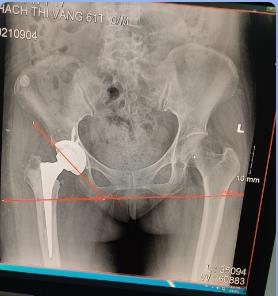

Thay khớp háng bán phần Thay khớp háng toàn phần với xi măng kháng sinh

không xi măng điều trị nhiễm trùng khớp nhân tạo không xi măng

- Thay lại khớp háng .